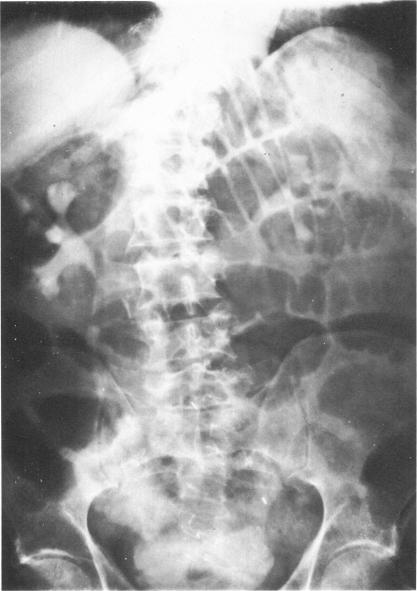

Experience with ileal ureters.

Bull N Y Acad Med. 1977 May;53(4):329-37.

PMID:266412

原文链接:https://pmc.ncbi.nlm.nih.gov/articles/PMC1807295/